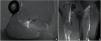

48 h after the injury an MRI was conducted, diagnosing a complete transversal rupture of the free tendon of the biceps femoris long head with retraction of the distal portion (Fig. 1).

MRI Hockey player. Axial (A) and coronal (B and C) proton density fat saturated images. In the axial view there is a complete transversal rupture of the proximal tendon of the long head of biceps femoris (arrowhead), in the coronal view (B) is shown the rupture (arrowhead) with proximal destructuring of the free tendon (thicker and hyperintensity) (arrow). In the more posterior coronal view (C), there is retraction of the distal portion of the rupture (arrowhead) with lost of tendon tension and lost of pennation angle.